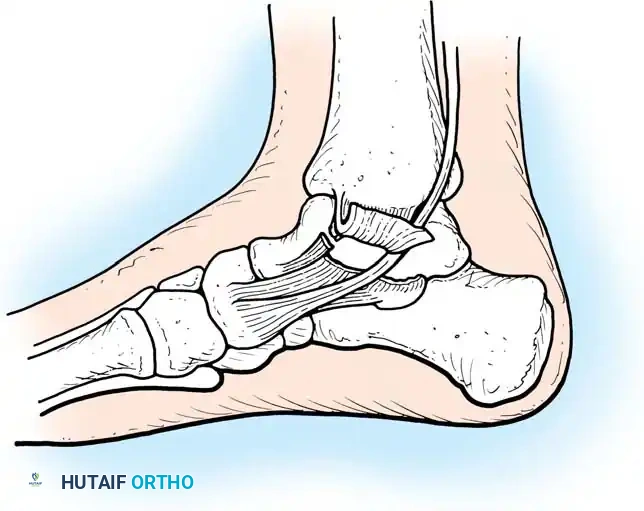

Lauge-Hansen correlated fracture patterns with the mechanism of injury, proposing a detailed classification system based on cadaveric studies. The first word in the designation refers to the foot’s position at the time of injury (supination or pronation); the second word refers to the direction of the deforming force relative to the tibia.

- Supination-Eversion (External Rotation) (SER): The most common mechanism. The identifying feature is a spiral oblique fracture of the distal fibula. It progresses in four stages: (1) disruption of the anterior tibiofibular ligament, (2) spiral oblique fracture of the distal fibula, (3) disruption of the posterior tibiofibular ligament or fracture of the posterior malleolus, and (4) fracture of the medial malleolus or rupture of the deltoid ligament.

- Supination-Adduction (SA): Characterized by a transverse avulsion-type fracture of the fibula below the level of the joint (or tear of the lateral collateral ligaments) and a relatively vertical shear fracture of the medial malleolus.

- Pronation-Abduction (PA): Involves a transverse fracture of the medial malleolus (or deltoid rupture), rupture of the syndesmotic ligaments, and a short, horizontal, oblique fracture of the fibula above the level of the joint.

- Pronation-Eversion (External Rotation) (PER): Begins with a transverse fracture of the medial malleolus or deltoid disruption, followed by anterior tibiofibular ligament disruption, a short oblique fracture of the fibula high above the joint level, and finally, posterior tibiofibular ligament rupture or posterolateral tibial avulsion.

The approach is via a standard longitudinal or slightly curved medial incision centered over the malleolus. Care must be taken to protect the saphenous vein and nerve. The fracture site is exposed, and any interposed periosteum or osteochondral debris is meticulously cleared.